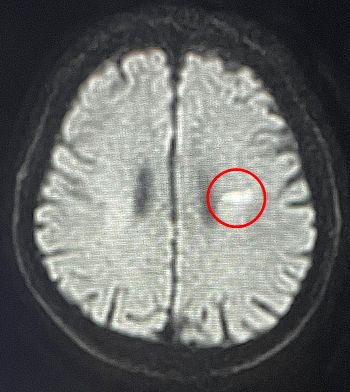

①脳やその周辺を撮影していきます。脳梗塞がある場合は白く眩しく光ります。

脳梗塞の実例(赤丸部分が白く光っている)